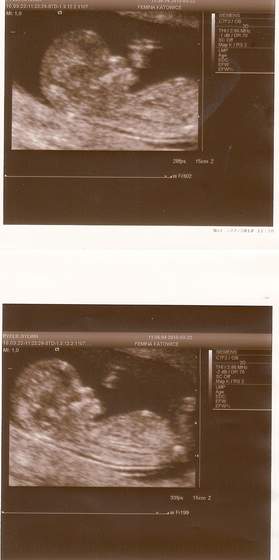

To moja kochana dzidzia skanuj0005..jpgskanuj0007..jpg usg w 12tyg+ 1 dzień